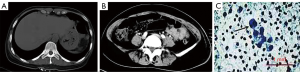

Physical examination at admission revealed an anemic appearance and a soft abdomen with mild tenderness and rebound pain in the right lower quadrant. Laboratory analysis revealed a red blood cell count of 2.37×1012/L (normal reference values: 3.8–5.1×1012/L) and a hemoglobin level of 58 g/L (normal reference values in women: 115–150 g/L). The white blood cell count was normal as well as the levels of the tumor markers carcinoembryonic antigen, CA125, and CA19-9. Human immunodeficiency virus test was negative. A contrast-enhanced computed tomography scan of the abdomen showed free intraperitoneal gas (Figure 1A) and the presence of a gas-liquid mixed density mass localized between the small intestine and sigmoid colon (Figure 1B). No intraluminal mass was found. The patient refused surgery and conservative treatment (consisting of cefmenoxime, 2.0, ivdrip, q12h) was then implemented. An abdominocentesis was performed, showing bloody fluid, and the exfoliative cytology test of the peritoneal fluid further revealed atypical tumor cells (Figure 1C).